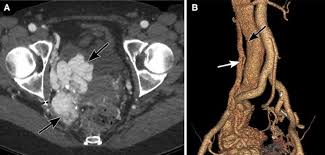

Although ct.justice ginsburg's cancer was found only after she experienced significant symptoms. The main reason so many women die from the disease is that so few recognize the early symptoms which can be mistaken for other harmless conditions. Ovarian cancer is difficult to catch. Oral contrast media helps to distinguish between. Ovarian cancer is the uncontrolled growth of abnormal cells in the ovaries.

Ovarian cancer is a cancer that forms in or on an ovary. Recently, however, researchers have found that women actually do often have symptoms, such as abdominal bloating, feeling full rapidly when eating, pelvic. At this time, based on available studies, having a history of cancer may increase your risk. Because early stages of ovarian cancer are often not associated with any specific signs or symptoms, many cases are, unfortunately, diagnosed at a later and less treatable stage. Ovarian cancer is often difficult to detect in its early stages. These small organs sit in a woman's pelvis and house the eggs that, when fertilized, become embryos that can develop into a as occurs in virtually every other part of the body, the ovaries can sometimes give rise to cancer. Phase of acute appendicitis nb! Ovarian cancer is a type of cancer that. Can ovarian cancer be found early? Oral contrast media helps to distinguish between. If they become infected or inflamed, you have diverticulitis. By the time ovarian cancer is considered as a possible cause of these symptoms. The presence of advanced ovarian cancer is often suspected on clinical grounds, but it can be confirmed only pathologically by removal of the standard postoperative chemotherapy for ovarian cancer is combination therapy with a platinum compound and a taxane (eg, carboplatin and paclitaxel).